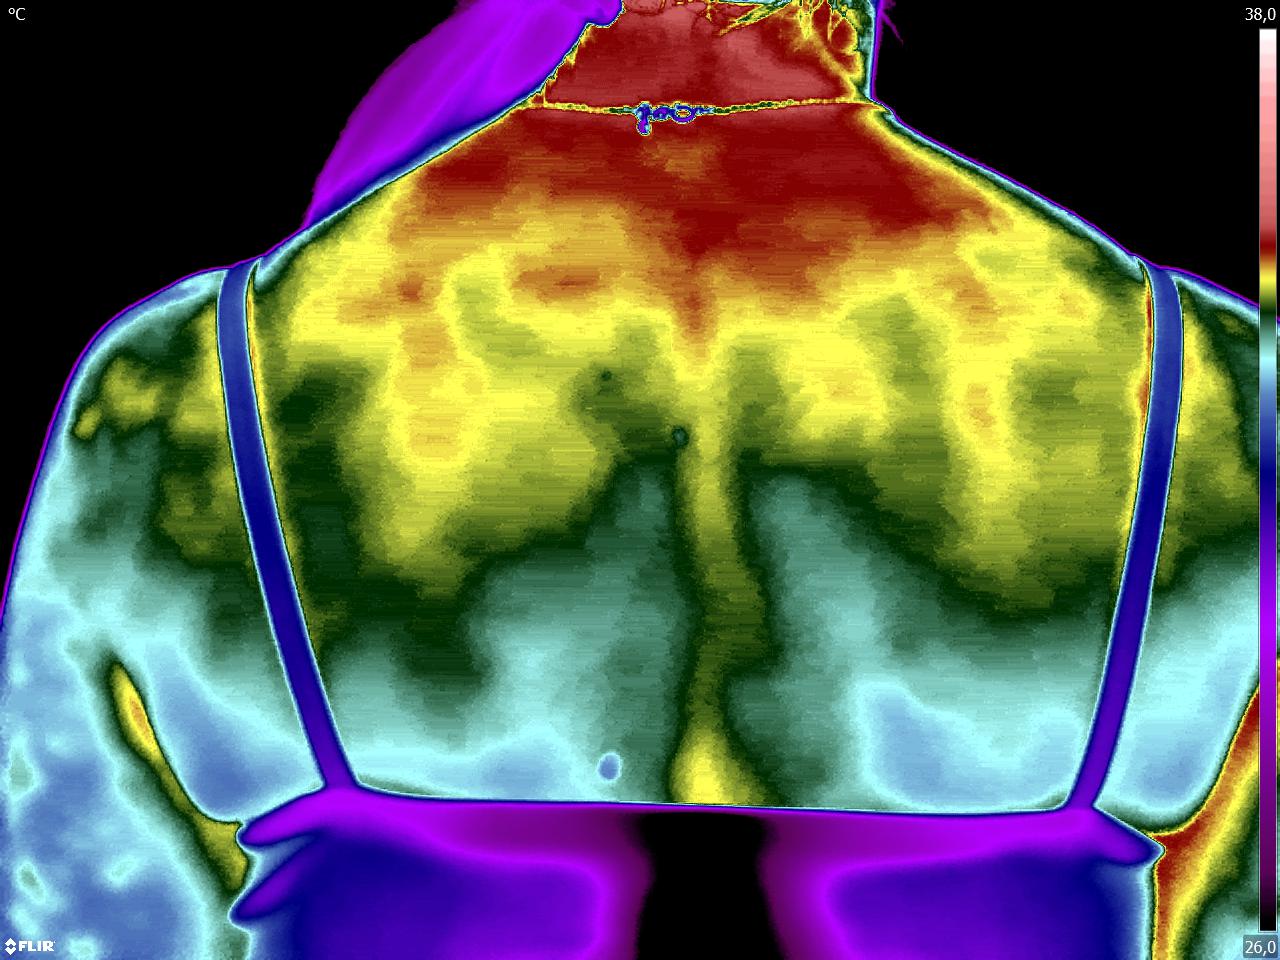

Caros colegas fisioterapeutas e terapeutas ocupacionais, vocês sabiam que, por meio do estudo da Termofuncional, é possível identificar alterações térmicas […]

Caros colegas fisioterapeutas e terapeutas ocupacionais, vocês sabiam que, com o estudo da técnica Termofuncional, é possível identificar alterações térmicas […]

Caros colegas fisioterapeutas e terapeutas ocupacionais, vocês sabiam que, por meio da técnica Termofuncional, é possível identificar alterações térmicas relevantes […]

Caros colegas, fisioterapeuta e terapeuta ocupacional, vocês sabiam que com a Termofuncional vocês podem diagnosticar disfunções e até lesões imediatamente […]